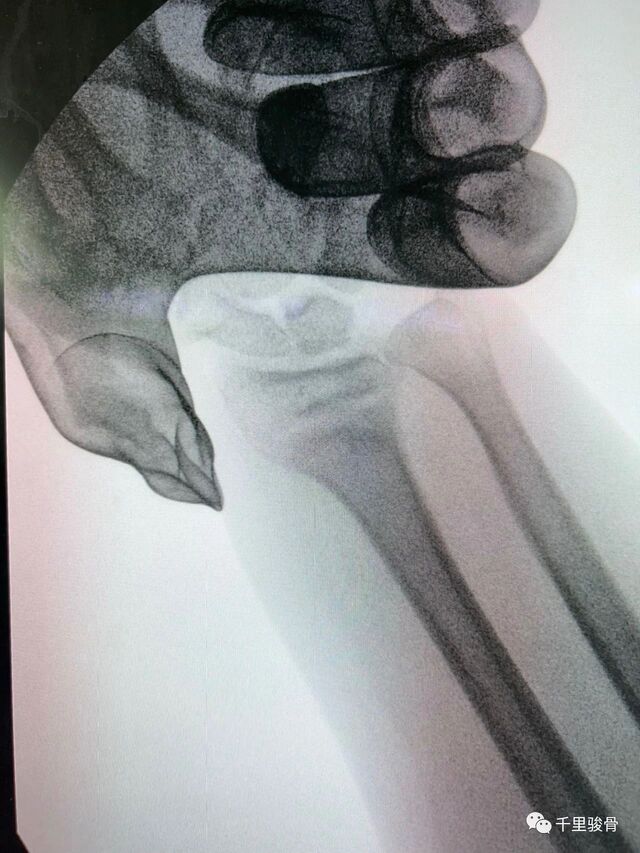

麻醉下透视复位

微信图片_20240102194812.jpg

微信图片_20240102194819.jpg